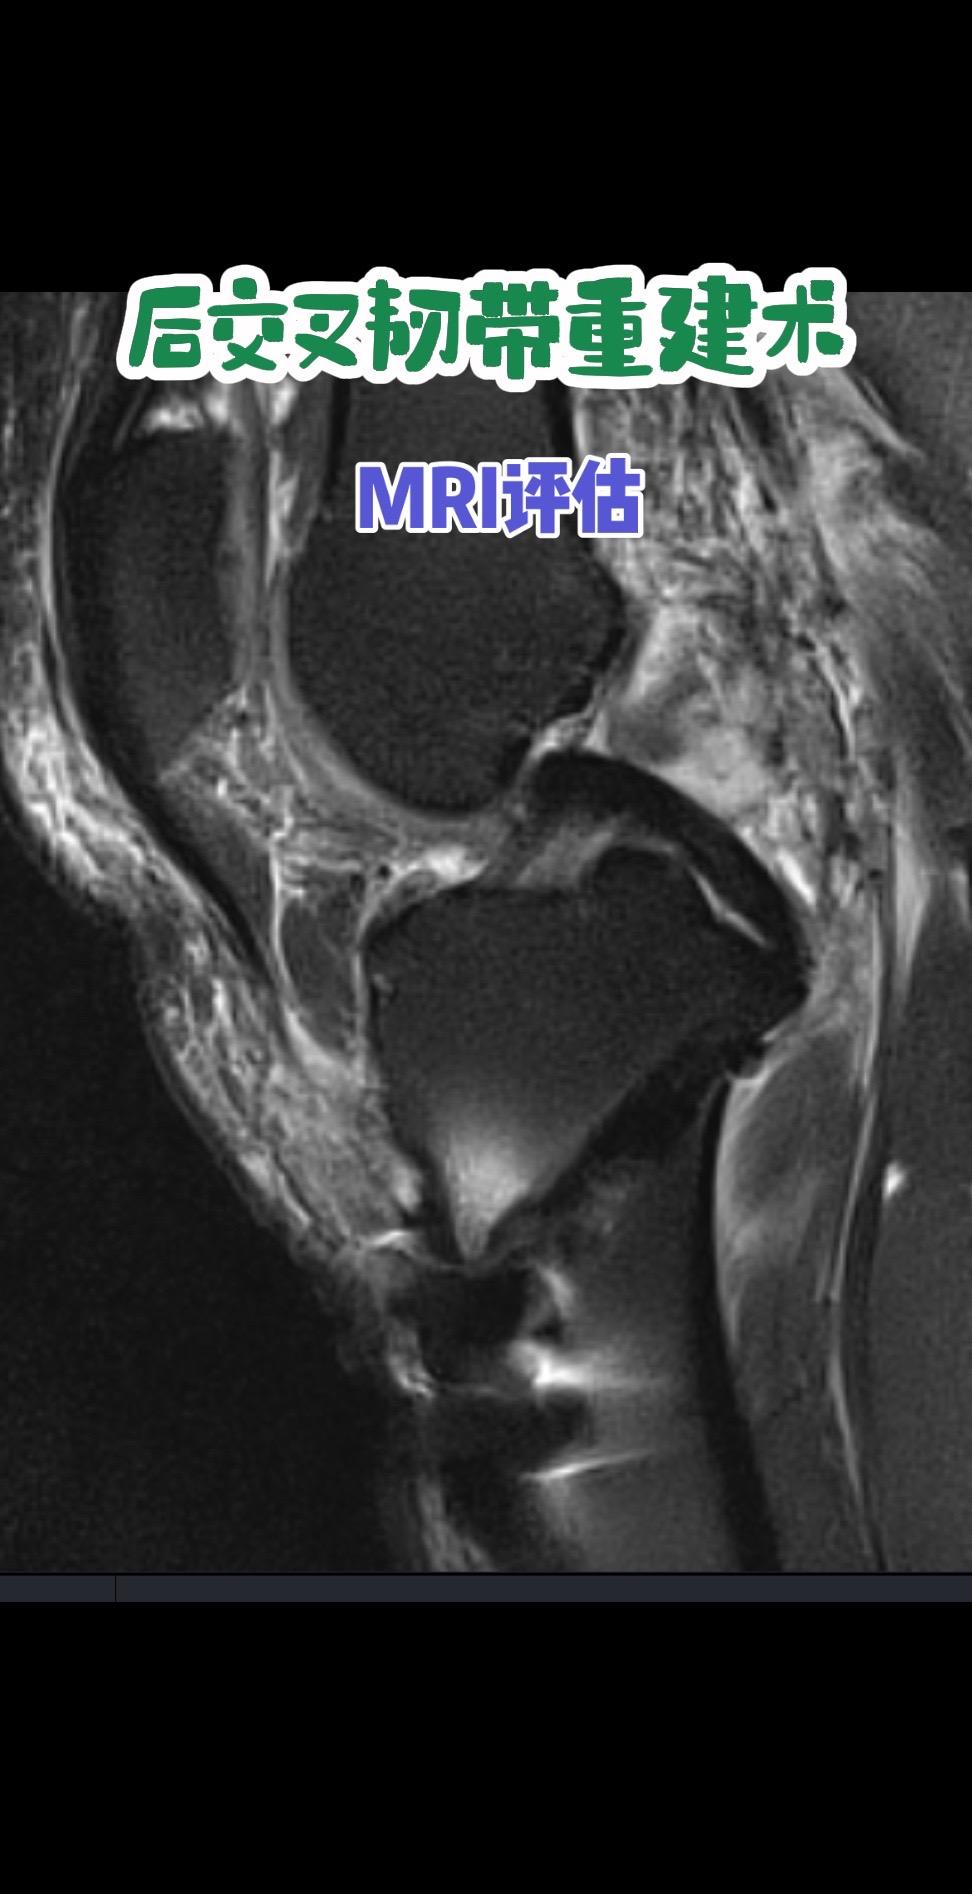

后交叉韧带重建术后影像评估。每一条韧带,都是膝盖的隐形安全带。而精准重建,就是给关节最可靠的浪漫守护。